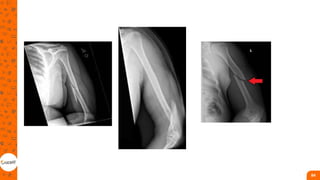

Fraturas em MMSS

• Correspondem a 42,8% de

todas as fraturas atendidas em

hospital;

• fraturas distais do rádio e da ulna

foram as mais comuns, seguidas

pelas fraturas dos ossos da mão

(falanges e metacarpos), pelas

fraturas proximais do úmero e

pelas fraturas de clavícula

• estavam presentes em 79,4%

dos acidentes domésticos,

69,9% dos acidentes de trabalho

e 94,1% dos acidentes de

trânsito

OMBRO

• Articulaçao mais móvel;

• Fratura proximal compromete

funcionalidade de todo membro;

• essas fraturas são causadas por

trauma direto, mas também, por

queda com a mão espalmada,

quedas de altura, acidentes

esportivos ou acidentes de